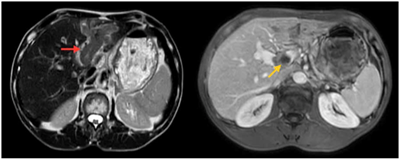

Ung thư thận là loại ung thư thường gặp đứng thứ 14 trên toàn cầu, với hơn 430.000 ca mới được chẩn đoán vào năm 2020, và 434840 ca mắc trên toàn cầu vào năm 2022. Tỷ lệ mắc thay đổi theo khu vực địa lý, cao hơn ở châu Âu và Bắc Mỹ. Ung...